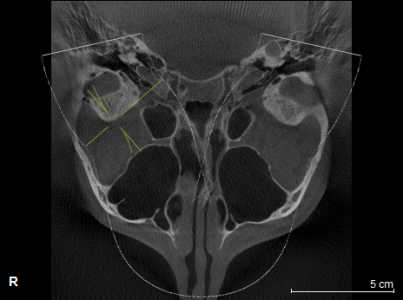

Здравствуйте! У моей дочери 16ти лет проблема с ВНЧС. При ношении брекетов ей вытягивали нижнюю челюсть, выравнивали прикус и зубы , в частности - клыки выпирающие выравнивали. А через 1,5 года после снятия в одно прекрасное утро не смогла открыть рот. Нам советовали делать лазер, становилось легче. Так было 2 раза. А теперь по утрам, если спит на правой щеке, то челюсть правую заклинивает. Голова сильно болит в висках. Связано ли это с брекетами или другая причина может быть? Читая в интернете об этой проблеме, поняла, что это дело очень тонкое и непростое, испортить жизнь ребенку можно запросто. А еще советуют мануального терапевта. Куда пойти ? У нас есть КТ в 3Д и еще нас на МРТ направили. Может ли мануальный терапевт решить эти проблемы? Знакомый стоматолог сказал, что если челюсть поправят, то прикус может нарушится. А мануальный говорит - приходите - все исправим, даже снимков ему не надо. .Теперь хочу выяснить у специалистов, как все таки поступить. К кому пойти сначала. Очень Вам буду благодарна за совет. Вот еще сделала скриншоты томографии